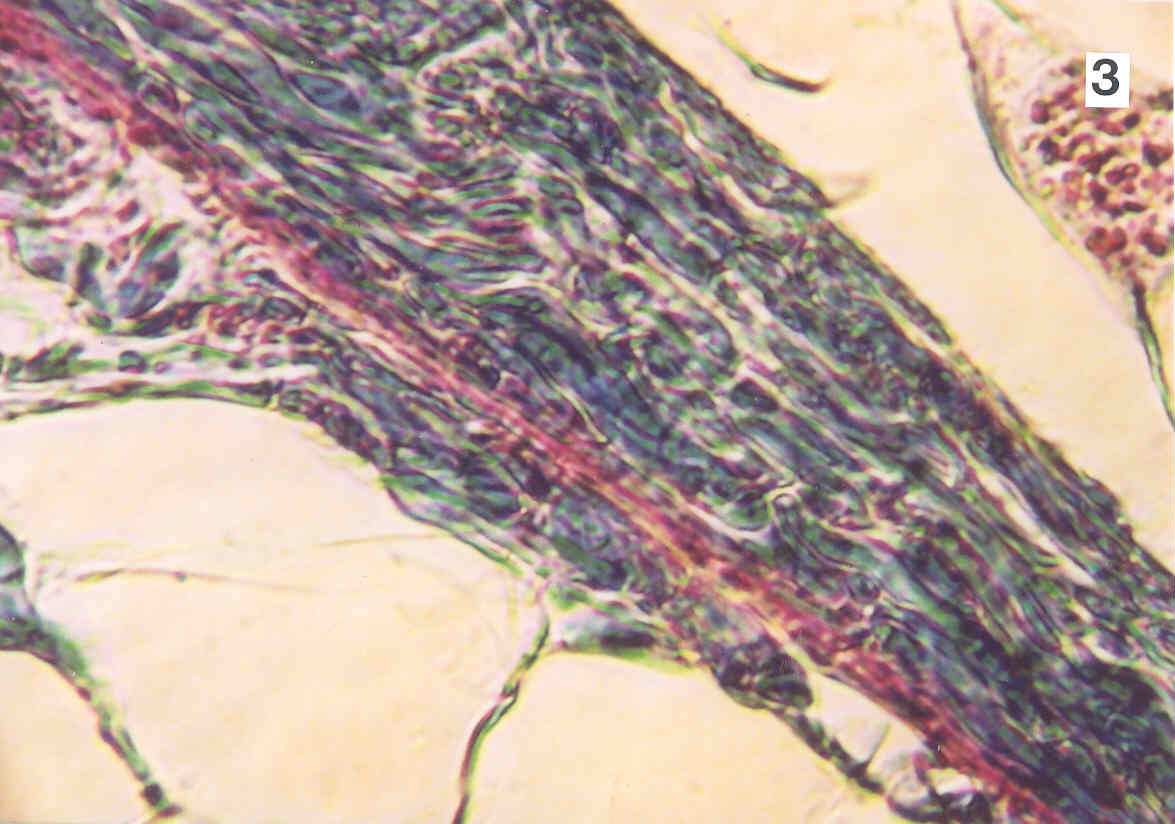

With the Grayfield microscopes, there is no interdependance between depth of field, magnification and resolution. Depth of field is adjustable between "very large" and "none" allowing for an image depth that was previously not possible.

By increasing the color contrast, all the structures can be seen clearly in their natural colors and with enhanced depth of field.